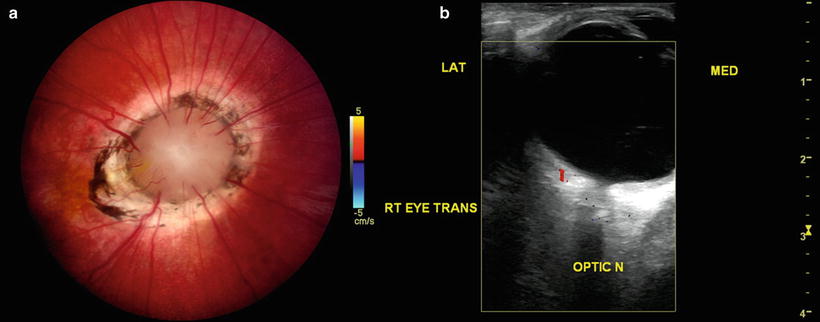

Moyamoya optic disc. (a) In the morning glory disc anomaly, absence of central retinal vasculature gives rise to compensatory collateralization of chorioretinal anastomoses (cilioretinal vessels) to also impart a “moyamoya” bypass system that is ophthalmoscopically visible within the distal optic nerve. (b) Color Doppler ultrasonography demonstrates the absence of vasculature within the central optic nerve. (From Brodsky MC and Parsa CF [64], with permission.)